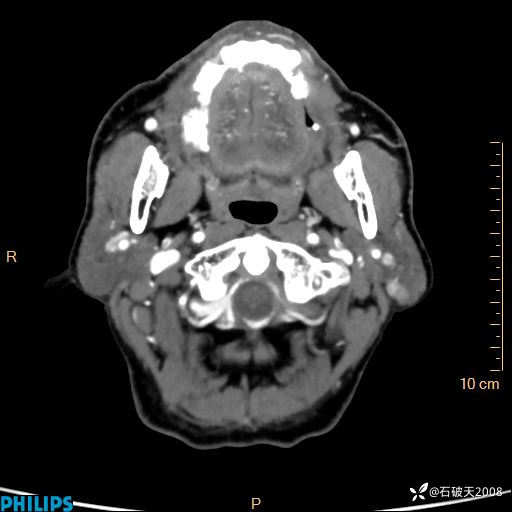

冠状位